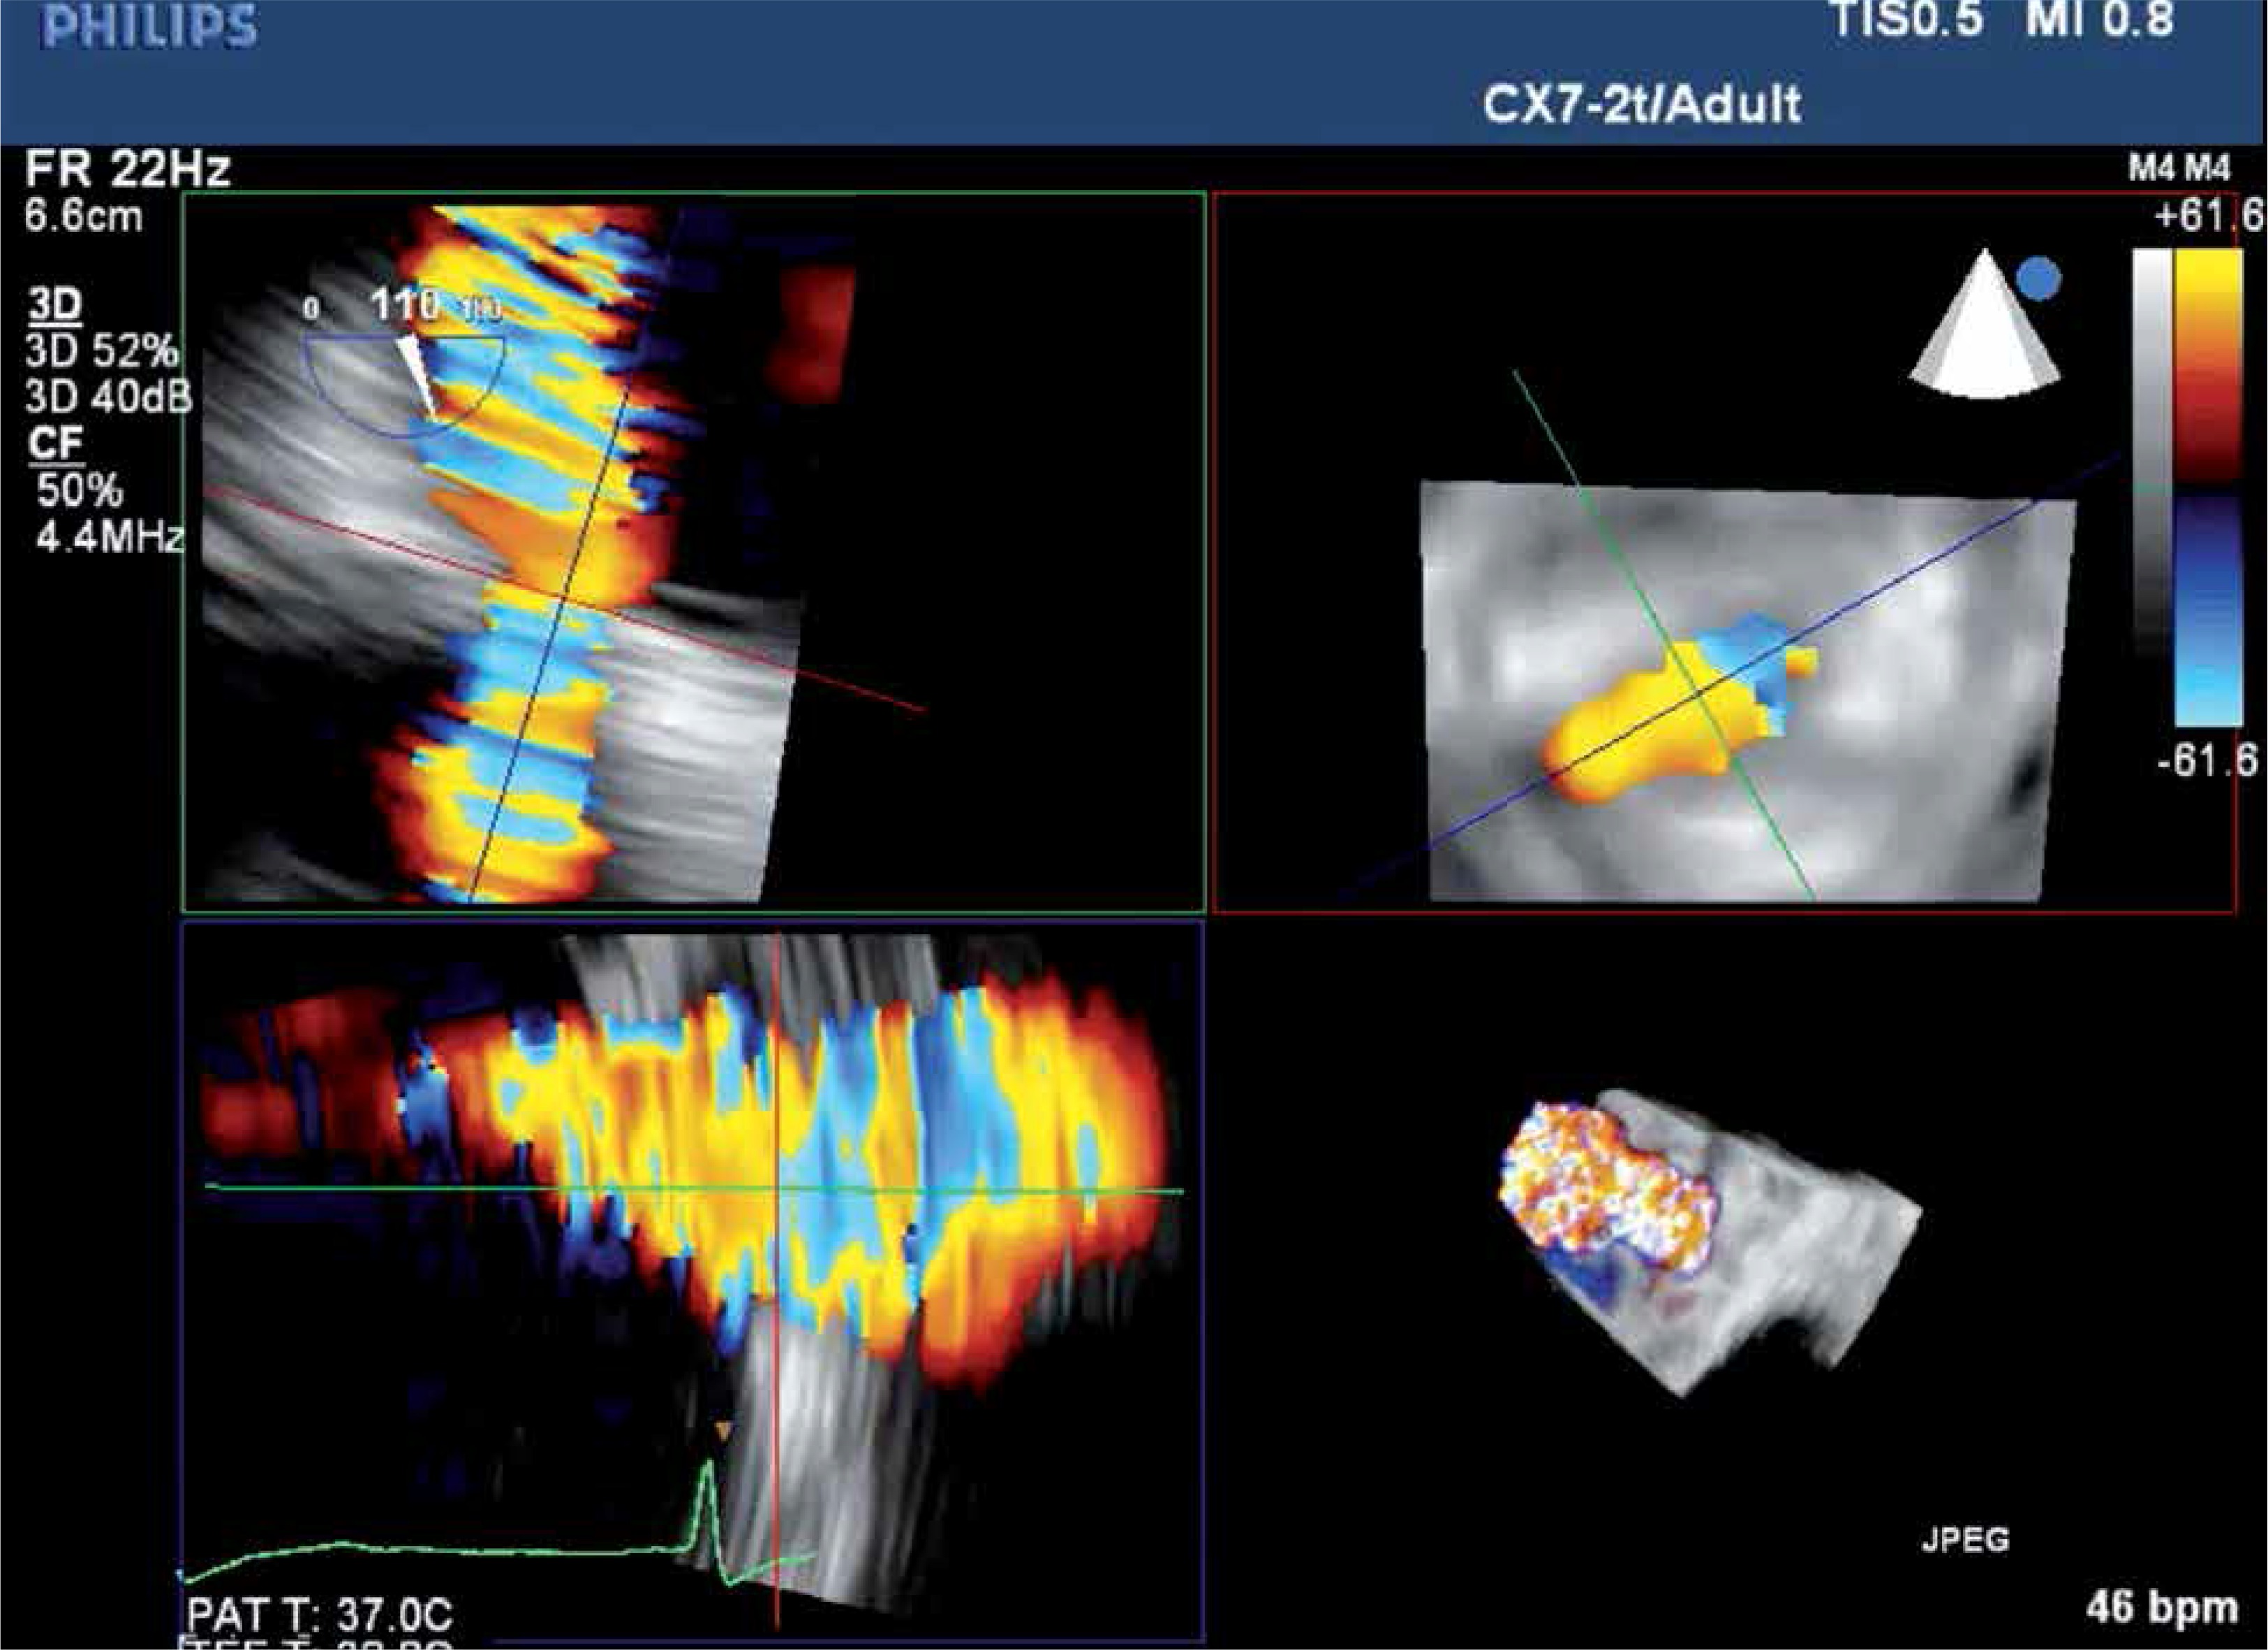

To ensure optimal spatial and temporal resolution, we acquire the smallest possible volumes containing the complete PVL channel in an ECG-gated, single-beat zoom 3D High Volume Rate (HVR) mode with color doppler (CD). Such visualization of PVL opacification by CD-mapped flow turbulence is used for detailed PVL anatomy analysis. With acquired volume being replayed in the multiplanar presentation the PVL channel is reoriented within the three perpendicular planes until two of them are positioned parallel to the flow direction while the third one is perpendicular and at the level of the vena contracta (VC) – Figure 1. Pivotal for the device choice are the cross-sectional area (CSA) and the minimum (width – W) and maximum (length – L) diameters of VC, all measured on the image frozen at the time of maximum paravalvular backflow. Analogously, the channel depth, understood as the distance between cavities of the left ventricle (LV) and left atrium (LA), can be verified (Figures 2 A and B). The size and number of plugs are chosen in previously described manners according to either CSA for AVP III [9, 11] or W and L for PLD [12].